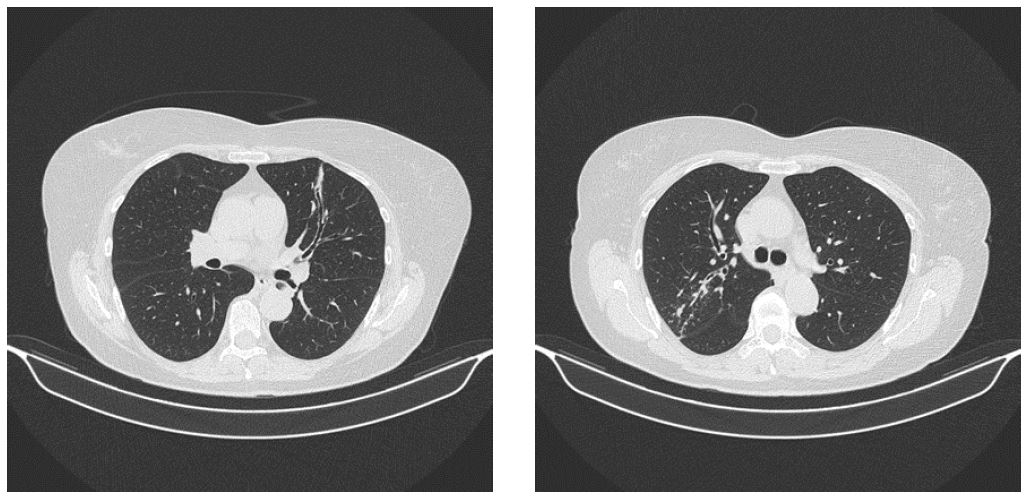

Диагноз установлен на основании характерной клинической картины приступов экспираторного удушья со свистящим дыханием, протекающих с упорным течением частично купируемых бронхолитиками, наличия на КТ ОГК от 15 июня 2022 г. специфических изменений (КТ-картина двухстороннего бронхиолита, ателектаза S5 правого легкого и субсегментарного ателектаза S4 левого легкого). Немногочисленные солидные очаги обоих легких, возможно, эозинофильные инфильтраты. Единичный увеличенный правый трахеобронхиальный узел. При сравнении с МСКТ от 03.02.2022 отмечалось появление ателектазов, бронхиолита и увеличение единичного лимфоузла, высокого уровня общего IgЕ = 979 ед/мл, положительного специфического IgE к Aspergillus fumigatus (1:600 (при норме 1:100)), выделение из промывной жидкости бронхов истинного мицелия микромицетов, при посеве рост Aspergillus fumigatus (рис. 2). Повышение специфических иммуноглобулинов G и М к аспергиллам.

Рис. 2. Пациентка Б. Компьютерная томография ОГК от 15 июня 2022 г.: картина двухстороннего бронхиолита, ателектаза S5 правого легкого и субсегментарного ателектаза S4 левого легкого. Немногочисленные солидные очаги обоих легких, возможно, эозинофильные инфильтраты. Единичный увеличенный правый трахеобронхиальный узел. При сравнении с МСКТ от 03.02.2022 – появление ателектазов, бронхиолита и увеличение единичного лимфоузла